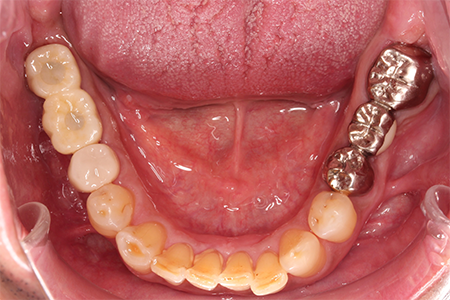

様々なことを鑑み、患者様とも何度も話し合いを行い、下の奥歯には必要最低限のインプラントを、他の歯も外科処置を施しなるべく歯を抜かない方法を取りました。

最終的に抜歯した本数は下の歯5本。上の歯に関しては全て残すことが出来ました。